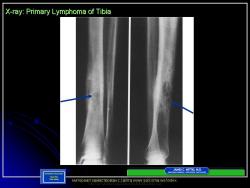

Более чем в 80% случаев лимфома кости локализуется в длинных трубчатых костяк нижних конечностей. Поражаются также подвздошные кости, позвонки, лопатки, кости черепа, ребра, грудина и надколенник.

Большинство авторов указывают, что у лимфомы кости нет патогномоничных рентгенологических признаков. В начальных фазах развития рентгенодиагностика лимфомы кости весьма затруднительна. Реакция периоста наблюдается редко и не имеет каких-либо характерных особенностей. Кортикальный слой разрушается на большем или меньшем протяжении, но не расплавляется, как при остеолитических опухолях типа остеогенных сарком. Классическим проявлением считается мелконоздреватая деструкция, создающая картину пористой, рыхлой, пятнистой кости. Мелкоочаговая деструкция — сравнительно ранний симптом и не всегда улавливается рентгенологически. При прогрессировании процесса мелкие очаги сливаются в обширные литические участки, которые при первичном обследовании больных являются причиной значительных диагностических трудностей [Нечволодова О. Л., 1971]. Иногда на фоне очага отмечается ячеистый рисунок с плотными четкими перегородками. В плоских костях преобладает литический компонент, лишь иногда по периферии сохраняются участки костной ткани с характерным разволокнением и ноздреватым рисунком.

До последнего времени большинство авторов считали, что при лимфоме кости никогда не бывает вздутия кортикального слоя, а периостальная реакция, если и развивается, то выражена очень слабо в виде тонких пластинчатых наслоений [Панов Н. А., 1965; Со1еу, 1950, и др.]. Однако в последние годы неоднократно описаны случаи лимфомы кости со слоистым, спикулообразным, кружевным и бахромчатым периоститом (Еремина Л. А.), М.С.Цешковский считает, что периостальная реакция при лимфоме кости всегда выражена, но в ранних стадиях, как правило, ее не обнаруживают вследствие прорыва опухоли в мягкие ткани. Вздутие кости отмечается редко, чаще у детей, связано по-видимому, из-за быстрого течения процесса.